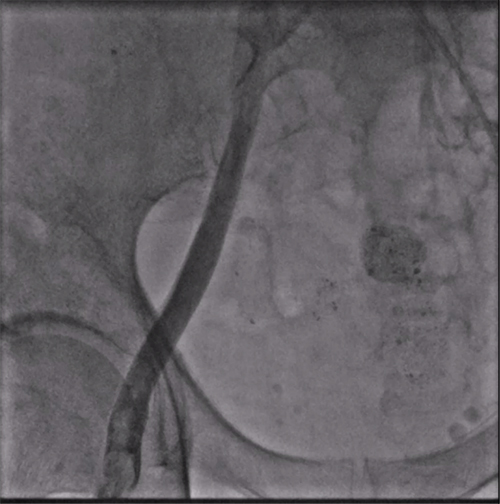

股静脉穿刺后下腔静脉造影